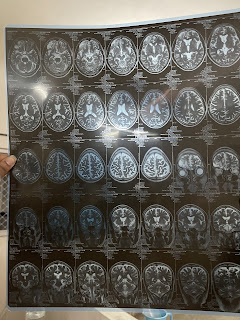

MRI Brain